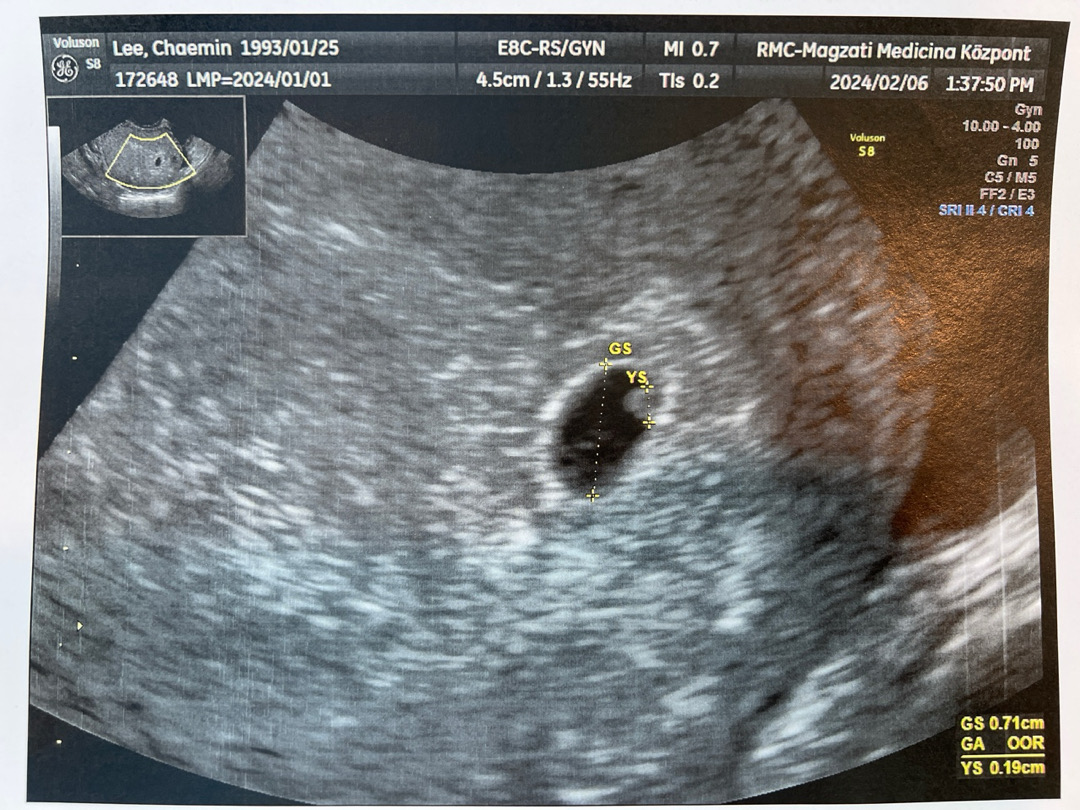

5주1일차 오늘 아기집이랑 난황봤어요!!!

외국이라 사실 반은 알아듣고 반은 소견서 봤는데 딱 주수만큼 잘 자라는 것 같아요❣️ 난황 볼 수 잇을까 걱정했는데 너무 잘 보이고 퍼펙트 하대요🥹🥹